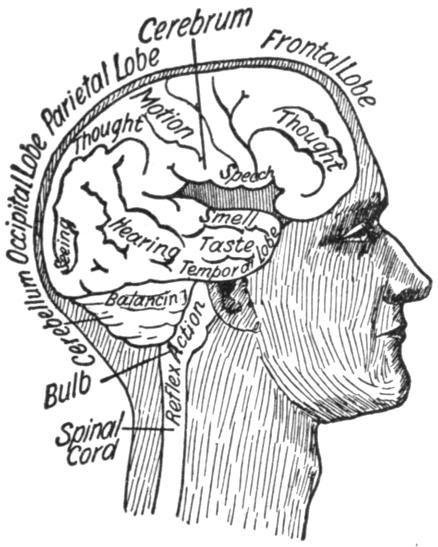

| VIII. | The Nervous System | H 117 |